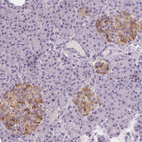

Immunohistochemical staining of human pancreas shows moderate cytoplasmic positivity in islets of Langerhans.